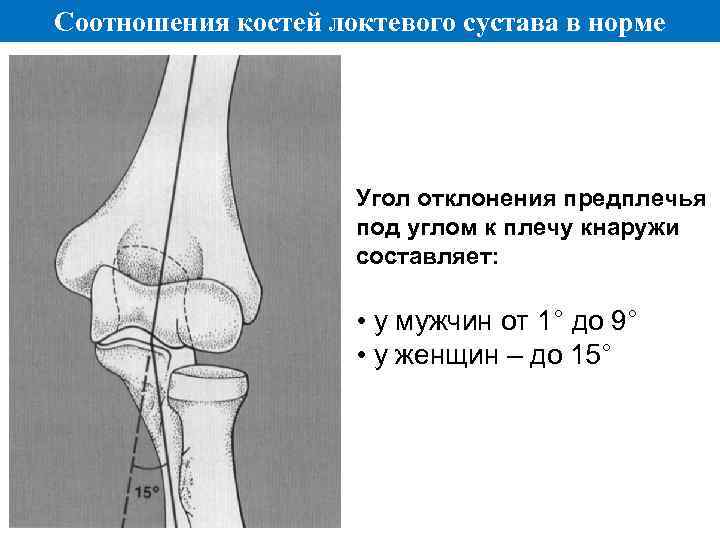

Соотношения костей локтевого сустава в норме Угол отклонения предплечья под углом к плечу кнаружи составляет: • у мужчин от 1° до 9° • у женщин – до 15°

Соотношения костей локтевого сустава в норме Угол отклонения предплечья под углом к плечу кнаружи составляет: • у мужчин от 1° до 9° • у женщин – до 15°